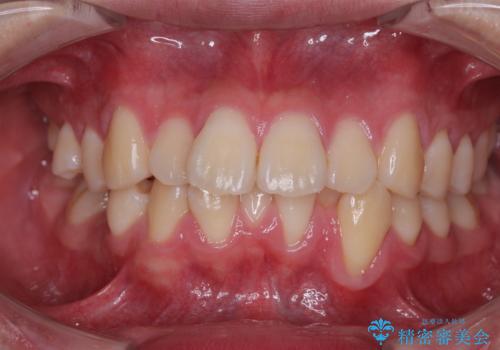

- 全顎的なデコボコを気にして来院された患者様です。

特に前歯のデコボコが顕著であり、上下左右第一小臼歯の4本を抜歯し、ワイヤー装置を使用して咬み合わせ高さを改善しながら、歯列を整えて行くこととしました。